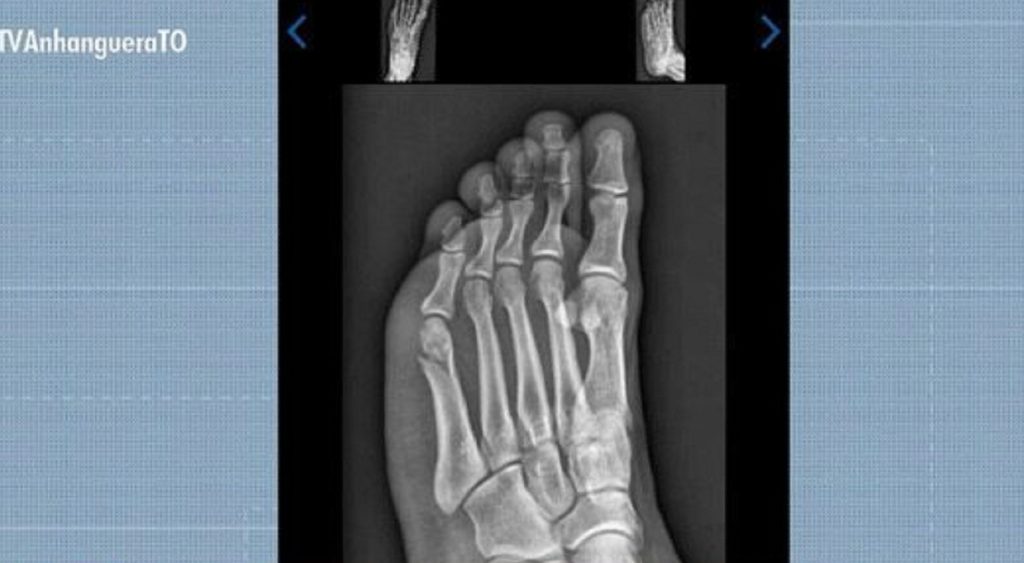

Gabriel Santos Rodrigues foi aprovado no TAF da PMTO mesmo com fratura no pé

Concurseiro concluiu prova de corrida do TAF com fratura no pé